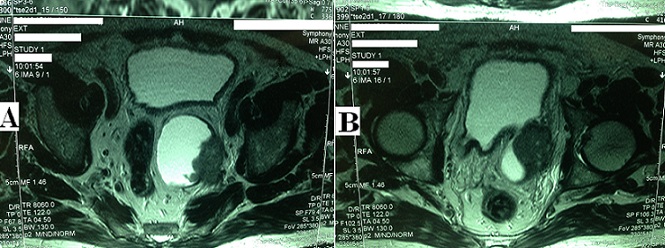

A 65-year-old man with a history of recurrent urinary tract infections presented after a 3-months of visible hematuria. Physical and laboratory examinations revealed anemia and impaired renal function. Ultrasound and magnetic resonnance imaging (MRI) showed an invasive bladder tumor developing in a large posterior diverticulum (A and B) with rectal deviation (A) and responsible of a left hydronephrosis. First, the patient underwent a blood transfusion and a left percutaneous nephrostomy. Two weeks later, we perfomed a cystoscopy and a transurethral resection of the tumor. Pathology revealed a locally advanced squamous cell carcinoma (SCC) (stage > p T2). The patient had no history of bilharziasis. Since the surgical extirpation was not possible, the patient was treated with chemoradiotherapy, but died 6 months later. Non-bilharzial SCC represents < 5% of vesical tumors, it is caused by chronic irritation of the urothelium and often diagnosed at an advanced stage. The intradiveticular location account for approximately 1% of all bladder tumors and make the prognosis poorer due to lack of muscle barrier. This case combine these two rares conditions.